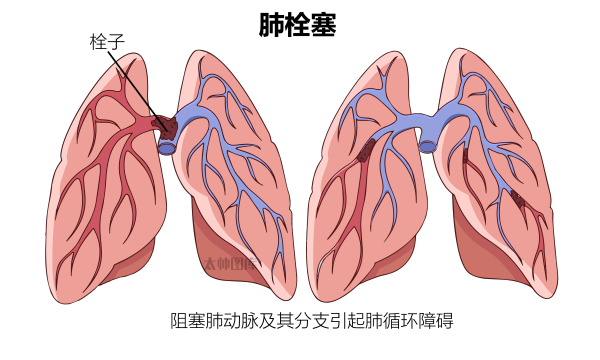

【图片来源:太帅图库】

肺栓塞是血栓阻塞肺动脉及其分支的急症,可能导致肺循环障碍、右心功能衰竭甚至猝死。常见症状包括突发性胸痛、呼吸困难、咯血等,不典型表现可能仅为晕厥、焦虑或咳嗽等。高龄、手术创伤、长期卧床、恶性肿瘤等都是高危因素。